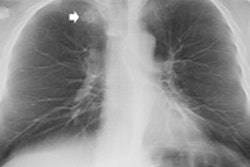

The group has been investigating whether DR tomosynthesis could eliminate the use of CT in some patients with suspicious pulmonary lesions by enabling lesions to be characterized as malignant or benign with DR alone. By creating 3D reconstructions from a series of 2D x-ray slices, tomosynthesis solves the problem of overlapping structures that frequently confounds traditional x-ray.

"Since the chest is a 3D structure, the problem with chest x-ray is every plane is compressed through the image," said Dr. Emilio Quaia and Dr. Elisa Baratella from the department of radiology at University of Trieste. "Tomosynthesis allows you to analyze every single plane of the volume, avoiding the overlap with the adjacent structure, including vessel, rib, and heart structure, which can sometimes create pseudolesions."